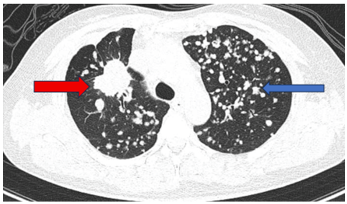

Bệnh nhân đi khám tại bệnh viện Bạch Mai được chụp cắt lớp vi tính lồng ngực phát hiện nhu mô thùy trên có khối đặc kích thước 40 x 35mm, các nốt đặc đường kính <12mm lan tỏa nhu mô hai phổi, ổ tiêu xương ức kích thước 31 x 13mm.

Hình 1: Hình ảnh tổn thương phổi trước điều trị: nhu mô thùy trên có khối đặc kích thước 40 x 35mm (mũi tên màu đỏ), các nốt đặc đường kính <12mm lan tỏa nhu mô hai phổi (mũi tên màu xanh)